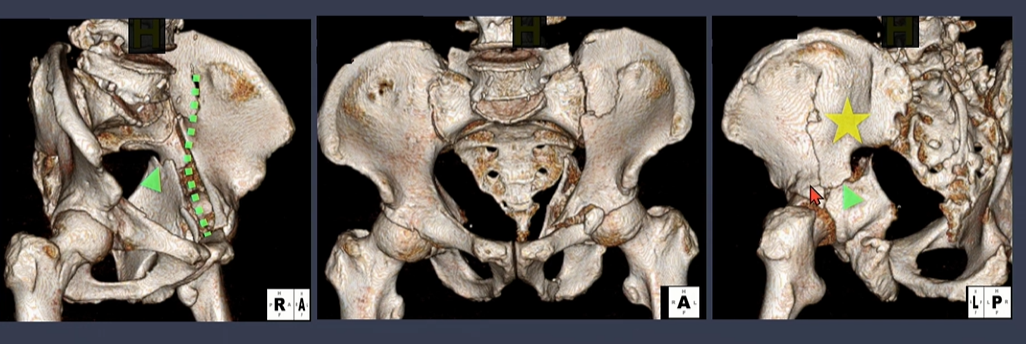

iliac wing쪽 골절선(녹색 점선)에 더해서, sciatic notch로 이어지는 골절선(녹색 화살표)을 확인.

노란색 별은 buttress 부위.

Spur sign은 both column fracture의 pathognomonic sign.